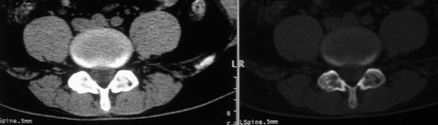

以下是引用余辉在2008-10-23 16:14:00的发言:[br]腰椎体棱角分明,小关节退变部分隔合,骶髂关节部分融合,考强脊炎